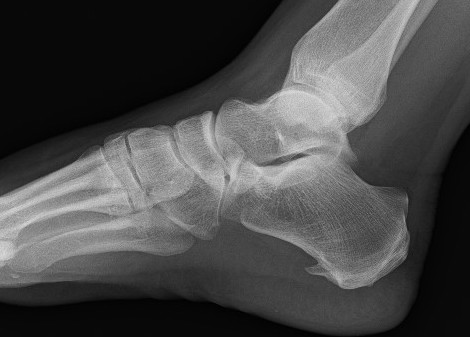

X-ray

Calcaneal spurs

Moroney et al Foot Ankle Spec 2014

- 1100 foot xrays

- calcaneal spurs in 12%

- more common women / older / diabetes / OA

- associated with foot pain

Zhou et al J Foot Ankle Surg 2015

- 2 types calcaneal spur

- Type A: superior to plantar fascia

- Type B: located within plantar fascia

Calcaneal spur above plantar fascia which is thickened with tears